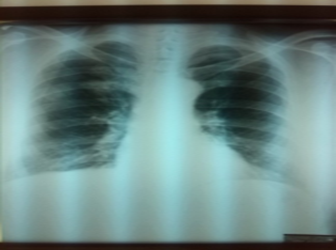

Picture 1

Lab findings on admission: SE 75/100, Le 14.2, Er 3.82, Hgb 122, Hct0.36m, Tr317, urea 9.1, creatinine 103.5, GGT 121.0, AST 31.2 ALT 71.7, ECG: sinus rhythm, fr 90/min, rs in D2, D3, aVF individual VES without changes in ST/T. An inhomogeneous round shadow can be seen on the X-ray image of the right subclavicular lung/picture 1/.